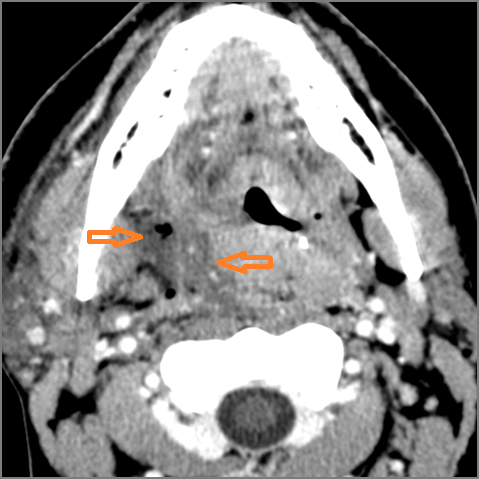

There is an abscess relatively centrally within the lymphoid tissue of the palatine tonsil. [Yes/No]

There is evidence of a developing abscess at the periphery of the lymphoid tissue of the palatine tonsil within the potential peritonsillar space. [Yes/No]

There is edema or abscess within the fat of the adjacent parapharyngeal and retropharyngeal space. [Yes/No]